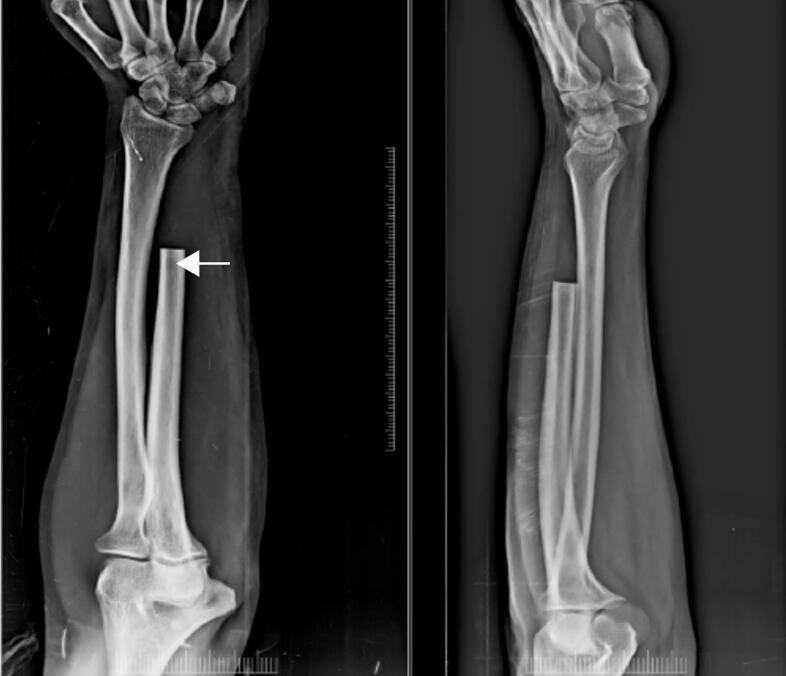

We present 2 cases of distal end ulna giant cell tumour (GCT). The first case involves a primary GCT in a young male, treated with marginal excision and extensor carpi ulnaris tenodesis, with no recurrence over three years. The second case describes a recurrent GCT in a middle-aged male, initially treated with curettage and bone cement in primary stage, followed by a successful marginal excision after recurrence.

Distal ulna giant cell tumours (GCTs) are uncommon, violent lesions that have a significant chance of recurring, particularly in Campanacci grade III instances. Stabilisation procedures such as ECU tendon reconstruction address post-resection issues such as discomfort, limited forearm rotation, and grip weakness, although en bloc resection is favoured to minimise recurrence.

Both cases highlight the challenges and considerations in managing distal ulna GCTs, emphasizing that en-bloc resection may reduce recurrence rates compared to curettage in grade III Campanacci GCTs.